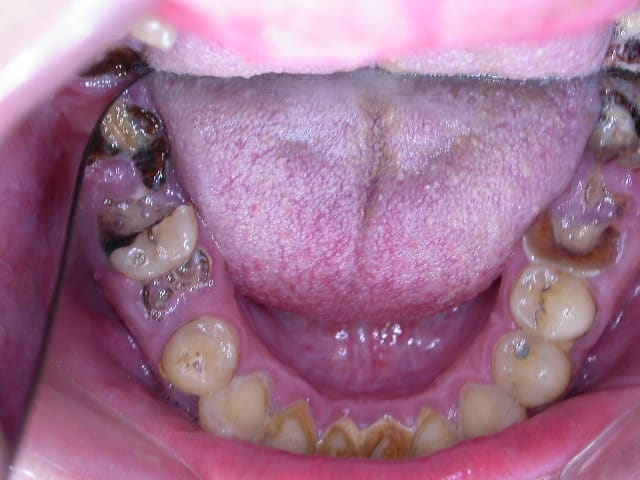

H47 ans avec un brossage annuel et une visite chez le dentiste par décennie.

Photo 023 e7liil - Eugenol

Photo 021 haqmw7 - Eugenol